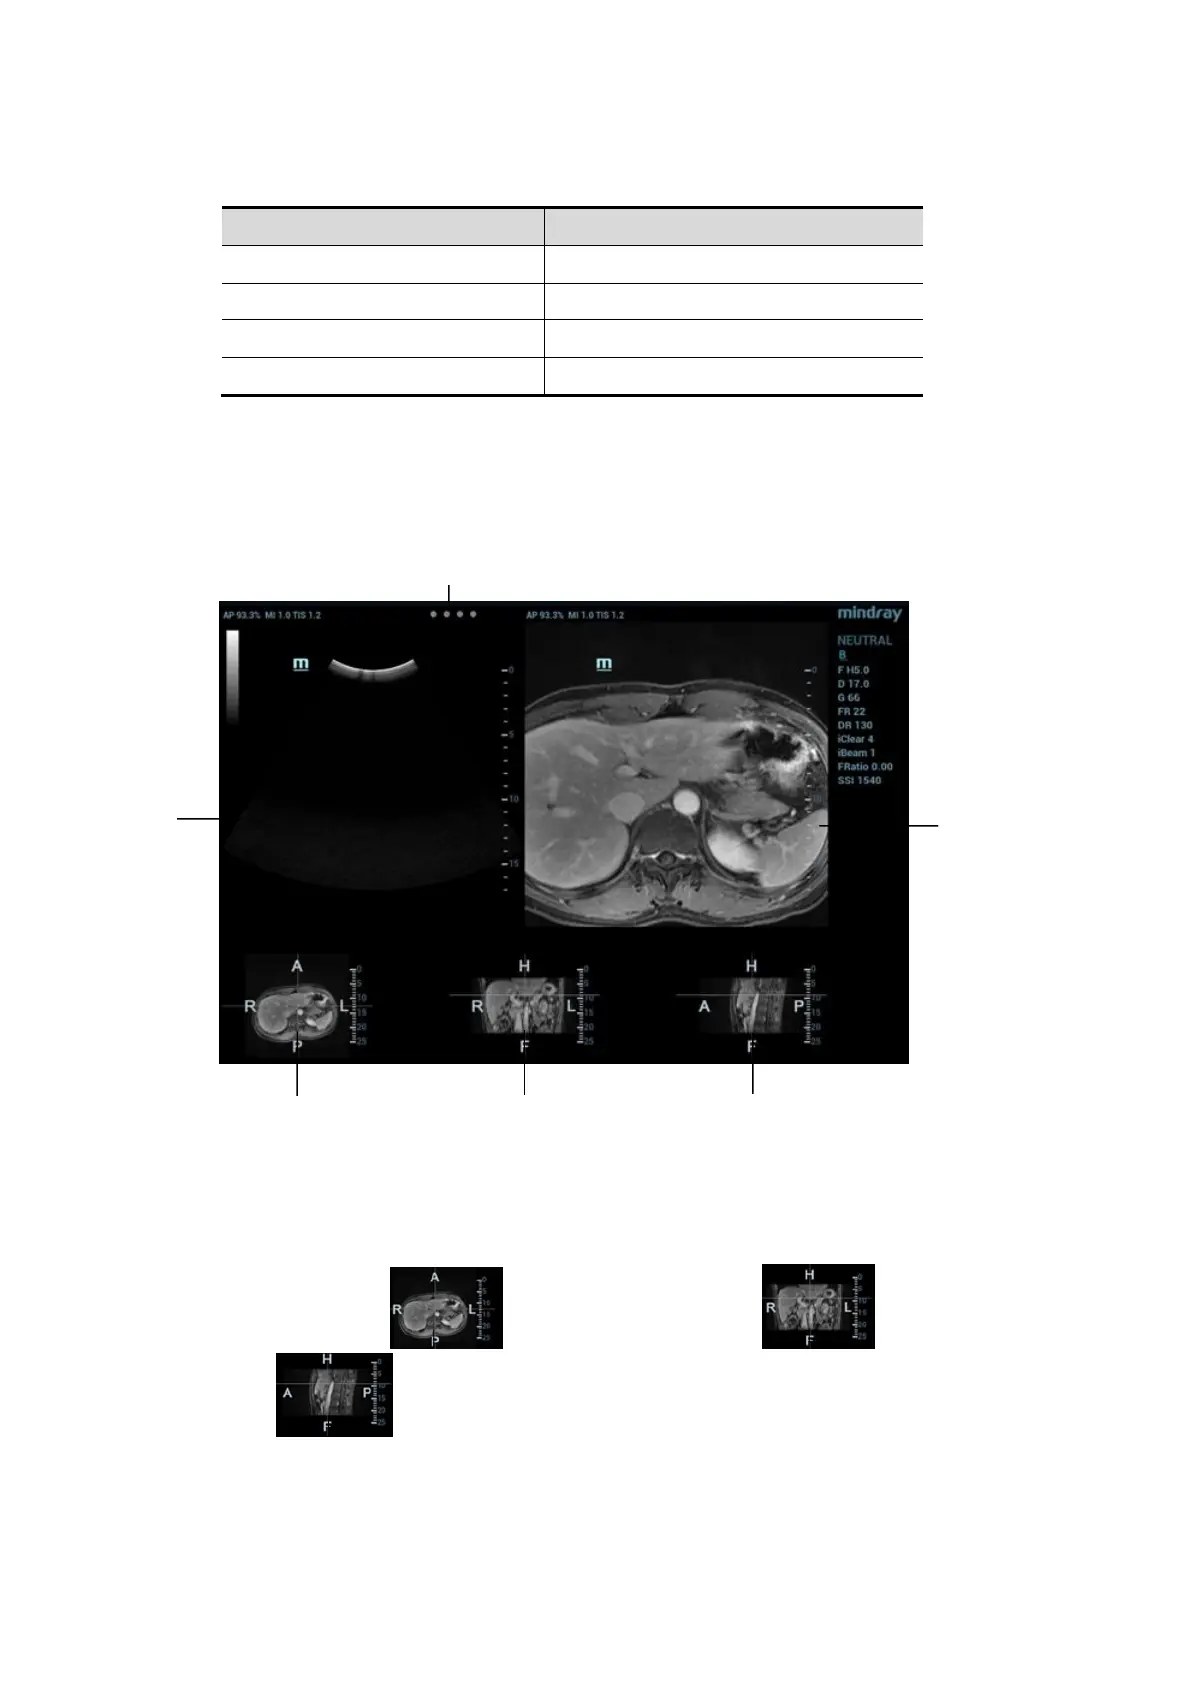

5.16.3 Screen Description

You should connect the magnetic devices, and then enter Fusion Imaging. The Fusion Imaging

screen appears. See Chapter 5.16.2 Magnetic Navigator for details.

3, 4 and 5 windows show the three anatomical planes of CT/MR 3-dimensional image (there are

transverse plane, coronal plane and sagittal plane respectively). The position for each plane is

shown below:

Each of them is:

R-L axis on transverse plane , A-P axis on coronal plane and H-F axis

on sagittal plane positioning in human body are shown below: